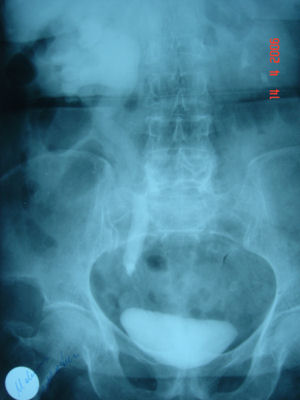

Radiology :

For every patient referred for stone or similar complaints, direct urinary system radiography (DUS) should be taken after the urine test and a complete abdominal ultrasonography (US) should be applied by considering the differential diagnosis.

As we specified above, 85% of the stones include Ca, therefore they may be seen in direct radiographies. US should also be taken to see whether a dilatation is present in the kidney.

If a final diagnosis can not be established by these two tests; Uropgraphy (IVP) taken by administrating colored agents intravenously or Computed Tomography (CT) with or without intravenous colored agent may be utilized.